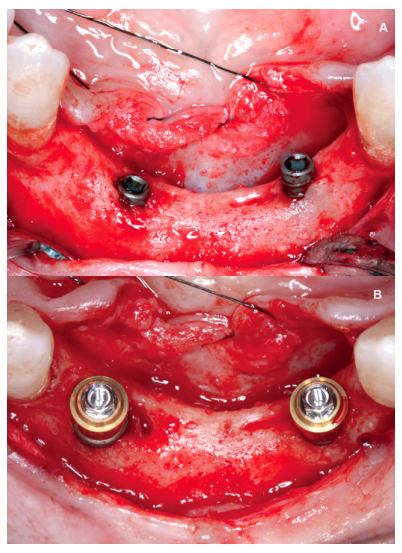

Currently in implant dentistry, we are increasingly faced with cases of extreme bone resorption that force us to implement different surgical dental implant techniques. The coexistence of vertical and horizontal atrophy makes successful resolution of these cases more difficult, as well as having to face these types of more complicated situations with increasing frequency, due to patients demanding implant treatment even in such very severe cases. It is not uncommon therefore to use combined techniques which include ridge expansion or short implants, for example. The following clinical case presented advanced horizontal and vertical alveolar atrophy in the right and left posterior regions of the mandible. The treatment plan included the use of short implants for the vertical atrophy and a two-stage alveolar ridge split to treat the horizontal atrophy.

Aft er 4 years, the second and third quadrant molars began to have excessive mobility and serious periodontal problems, so it was decided to remove them and regenerate the alveoli with PRGF-Endoret. Once the area was regenerated (a month and a half later), a conebeam was performed to evaluate the residual bone volume. It can be seen how there was an uneven bone crest with areas of 3.3 mm in height up to a maximum of 7 mm (Figures 9 and 10). On this occasion, due to the protocol change described above, we opted for the direct insertion of extra-short implants, since the surgical protocols to address this type of situation in 2011 varied substantially, with these implants being a first-line tool for the treatment of this type of atrophy (Figure 11). Two extra-short implants were selected (5.5 mm diameter x 6.5 mm length for tooth 26, and 6 mm diameter x 5.5 mm length for tooth 27).